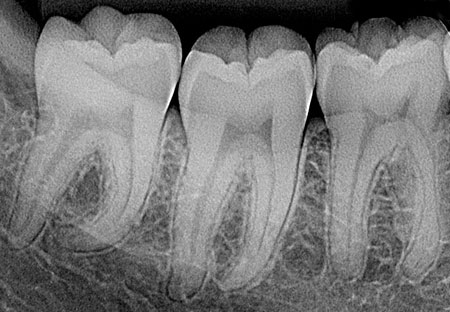

Radiografía Periapical

Permiten evaluar fracturas dentarias, lesiones cariosas y las alteraciones que comprometen la raíz del diente, el espacio periodontal y el tejido óseo que lo rodea.